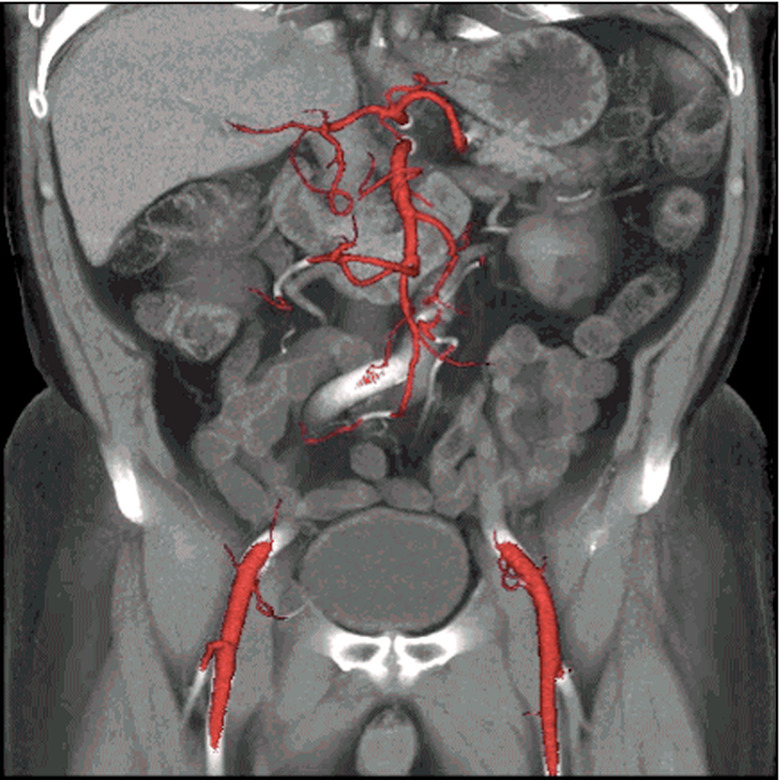

Few people enjoy having a CT scan. In a bleak hospital room, you have to lie flat on your back as a huge circular scanner shoots focused X-rays through your flesh and bones. The entire process can feel a little intimidating, which is why GE Healthcare has come up with the Revolution CT: a whisper-quiet and super-fast scanner that could make medical appointments a little quicker and less stressful for patients. The new machine, which is being trialled by the West Kendall Baptist Hospital in Florida, can capture an entire heart in a single beat, where each rotation takes just 0.28 seconds. That speed, combined with better contrast detection and noise reduction, could also reduce the doses of radiation required in each scan, potentially easing people's fears. In addition, none of these advancements should compromise the quality of the final 3D images — to prove its point, GE Healthcare has released some kinda gross, but undeniably beautiful GIFs of people's innards.

[Image Credit: GE Healthcare]